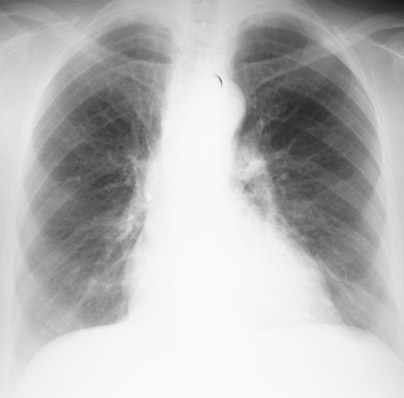

2) What is the most likely diagnosis on the following chest x-ray?